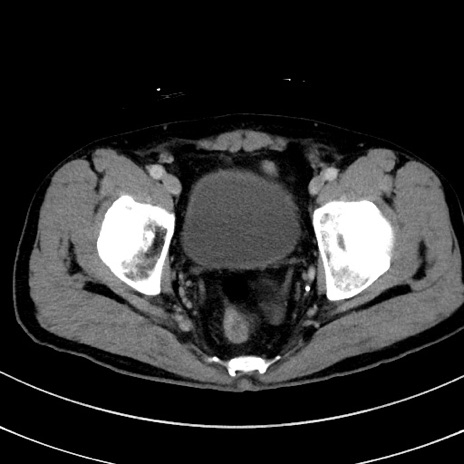

症例8(横断像)

【症例】 60歳代男性

【主訴】 黒色吐物

【現病歴】 4日前から嘔気自覚、2日前の朝食後にも嘔気あり、自分で手で嘔吐反射起こし嘔吐したところ血が混ざっていたため受診。

【既往歴】 5年前汎発性腹膜炎を伴う急性虫垂炎で手術、高血圧、前立腺肥大症、高脂血症

【身体所見】 腹部正中に手術癩痕あり 腹部平坦・軟圧痛なし膨満感あり

【データ】WBC 8400、CRP 4.54